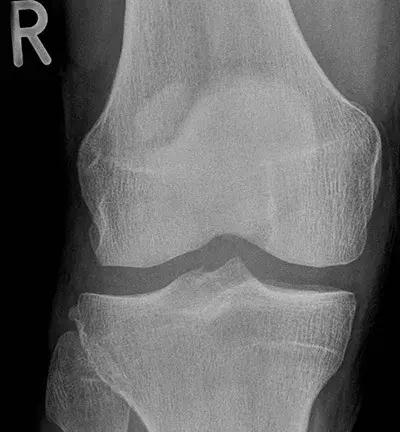

图1 X片

因X片检查不敏感,看不出此类隐匿骨折(图1),不推荐。MRI(核磁共振成像)对应力骨折的裂缝及周围水肿比较敏感(图2),作为首选检查。